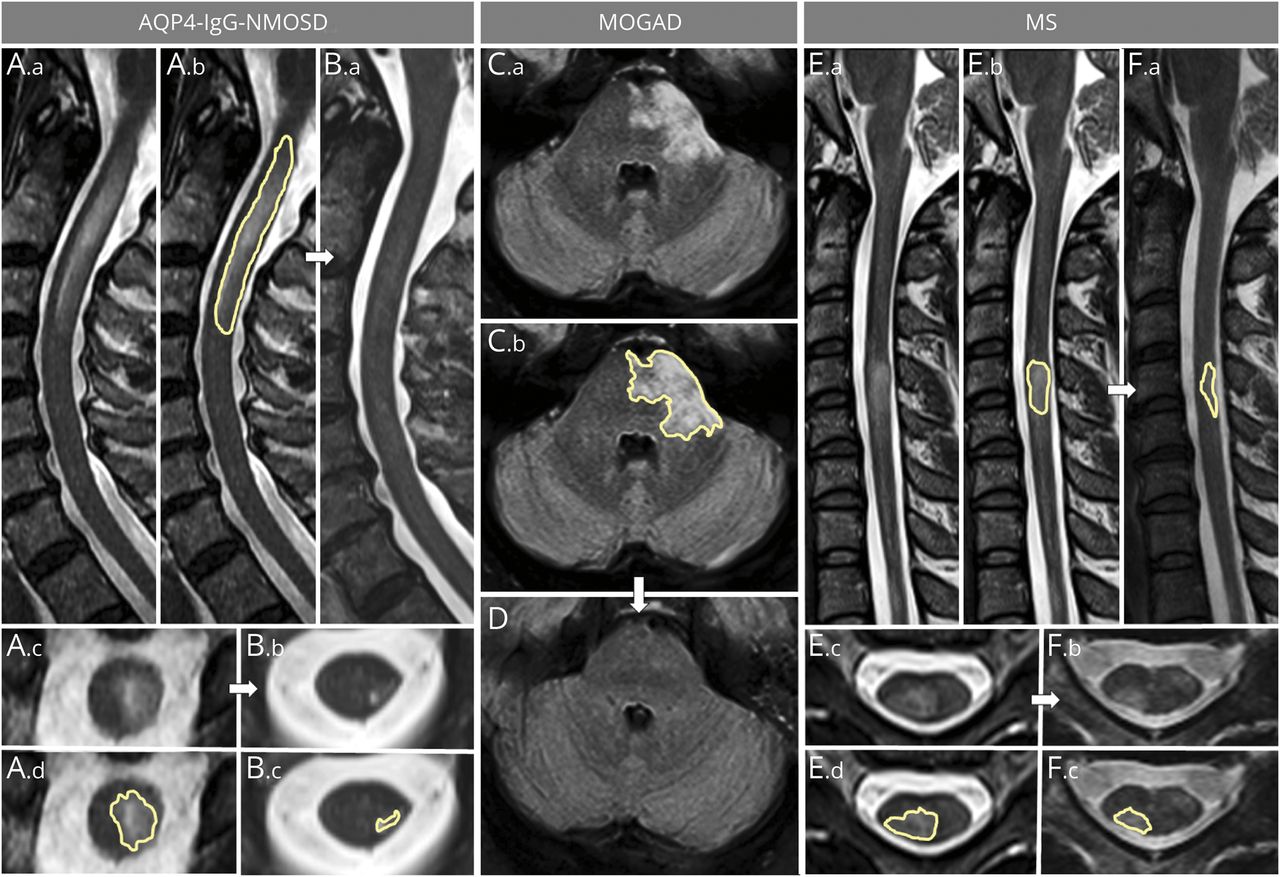

矢状(A。a、B。a, C。a, D。a, E。F。a) and axial (A.b, B.b, C.b, D.b, E.b, F.b) thoracic spinal cord T2-weighted images are shown. In patients with myelitis, T2-hyperintense lesions associated with AQP4-IgG-NMOSD, longitudinally extensive lesions with swelling of the spinal cord (A.a) and holocord involvement acutely (A.b [T7 vertebral body level]), frequently show a dramatic reduction in size at follow-up MRI but remain detectable, often accompanied by focal lesional spinal cord atrophy (B.a, B.b [T7 vertebral body level]). In patients with MOGAD myelitis, the acute ventral-predominant long T2 lesion extending to the conus (C.a) is gray matter restricted axially (C.b [T3 vertebral body level]) and resolved completely at follow-up MRI (D.a, D.b [T3 vertebral body level]). In patients with MS, the typically short acute myelitis T2-hyperintense lesion (E.a, E.b [T6-T7 vertebral body level]) often only has modest reduction in size at follow-up MRI (F.a, F.b [T6-T7 vertebral body level]), at which time it can be better appreciated to involve the periphery (right lateral columns) of the spinal cord on axial images (F.b [T6-T7 vertebral body level]).